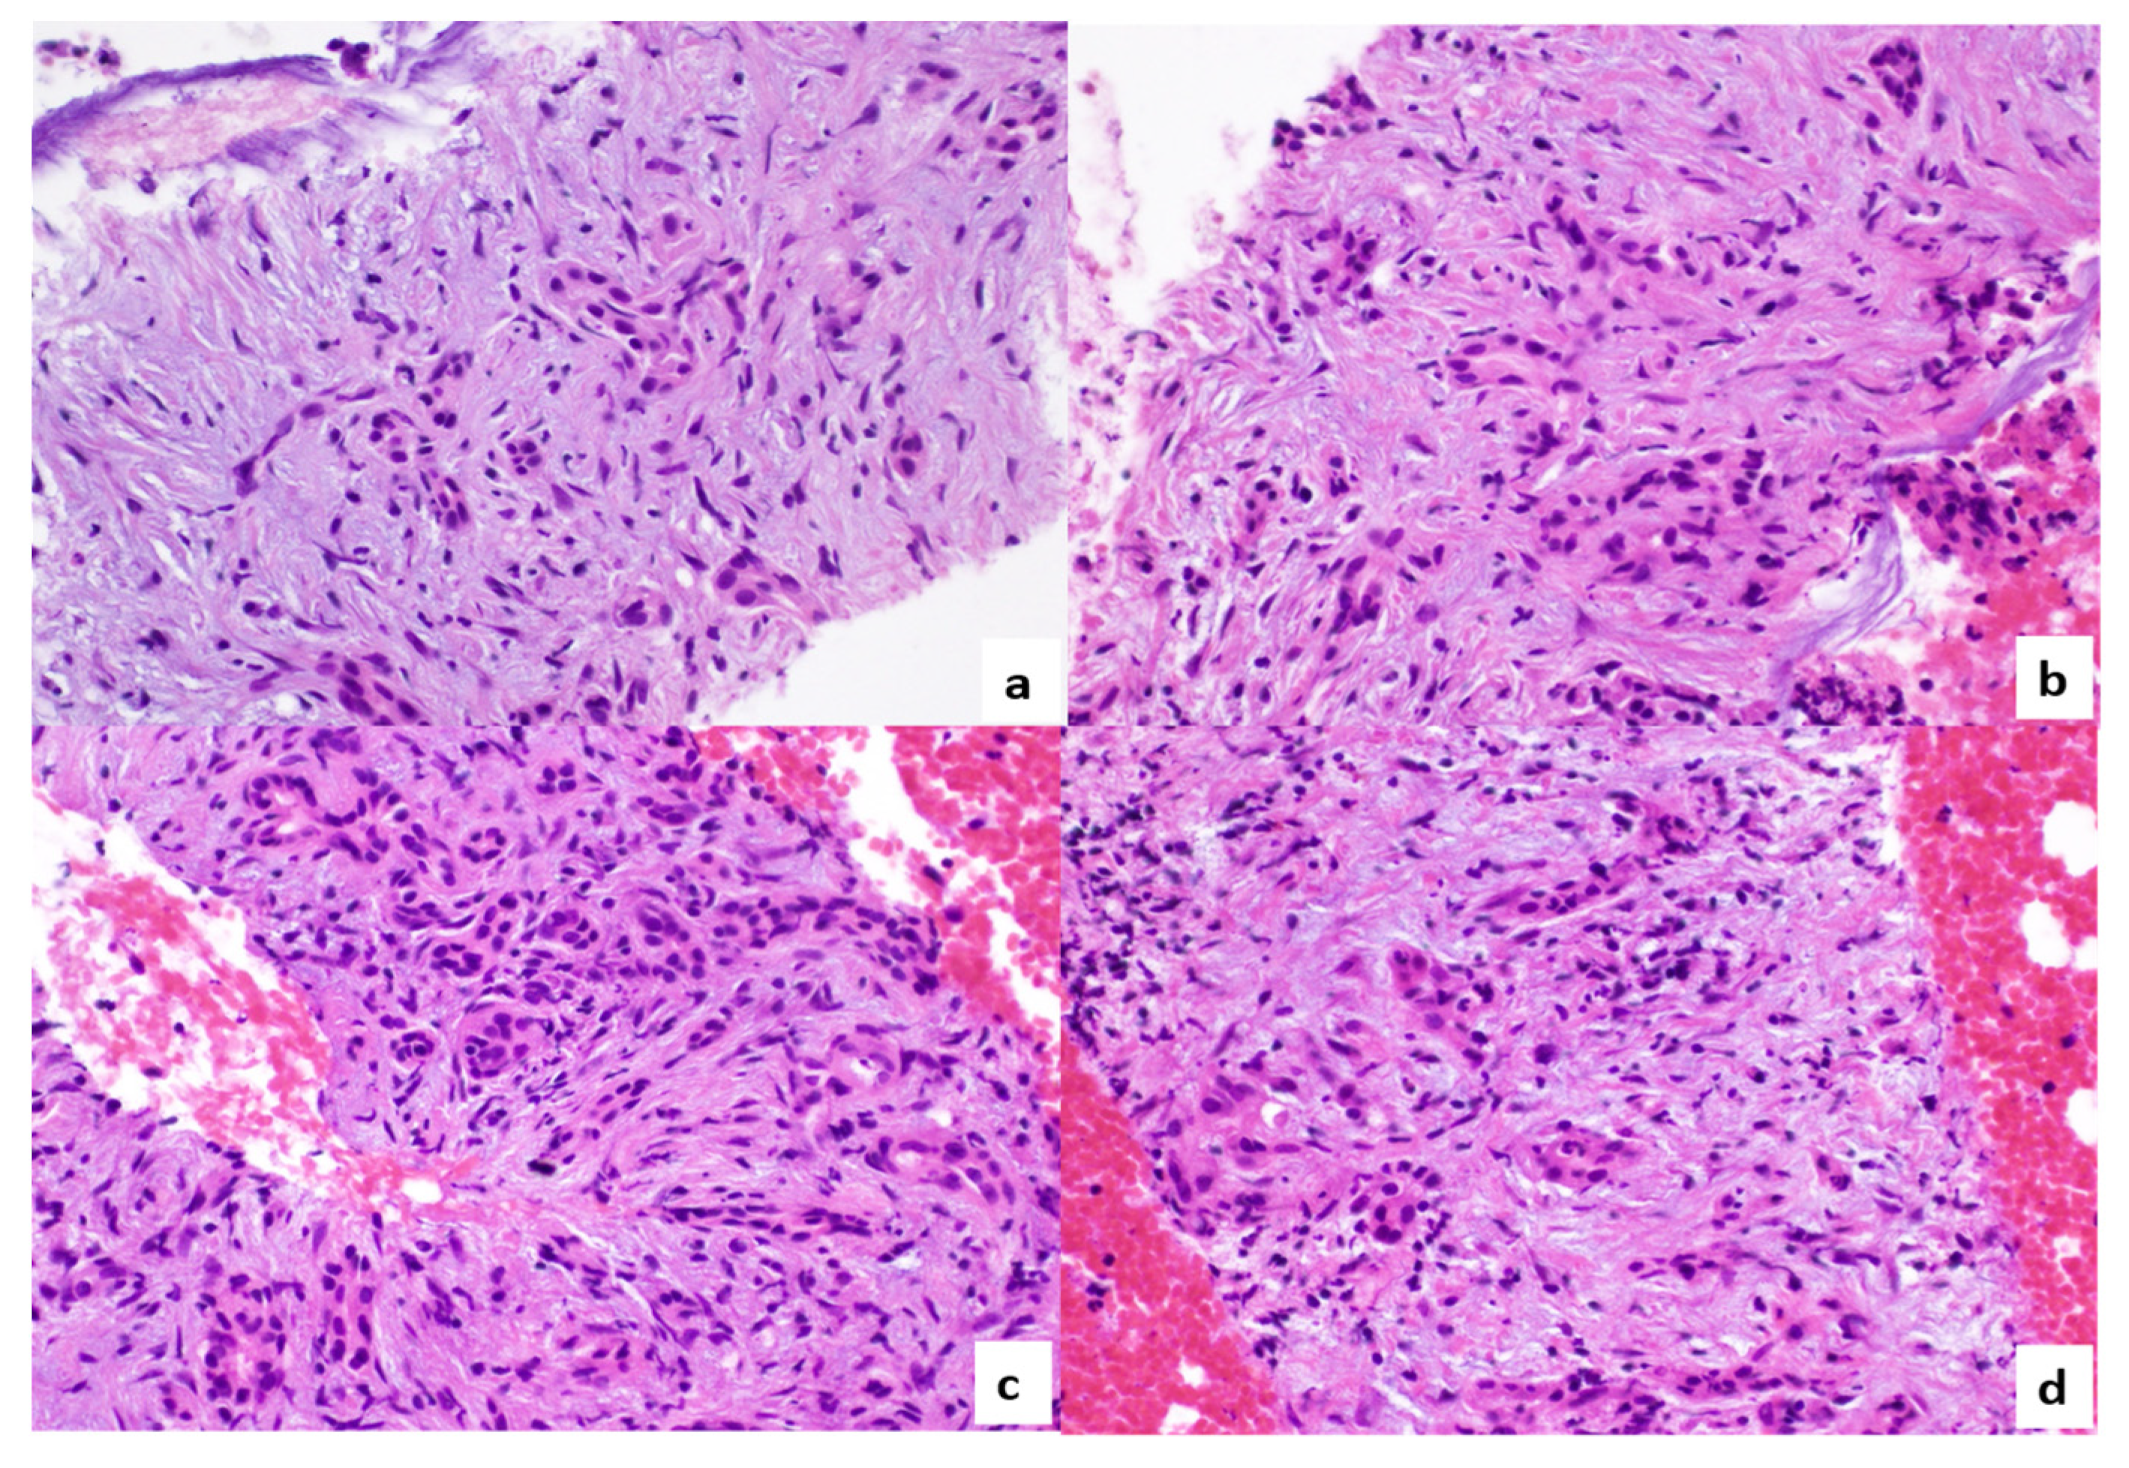

2. Case Report